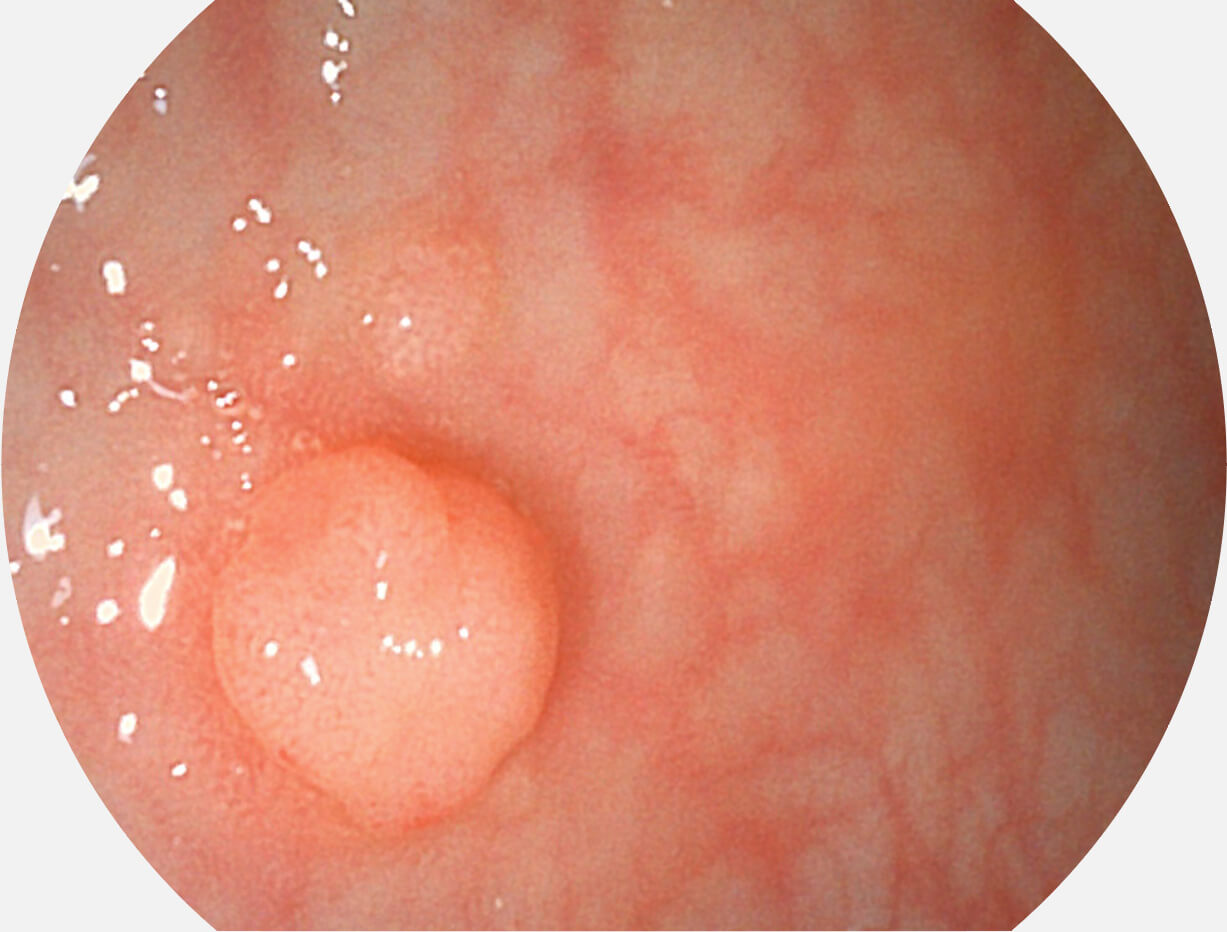

白光图像

VIST图像